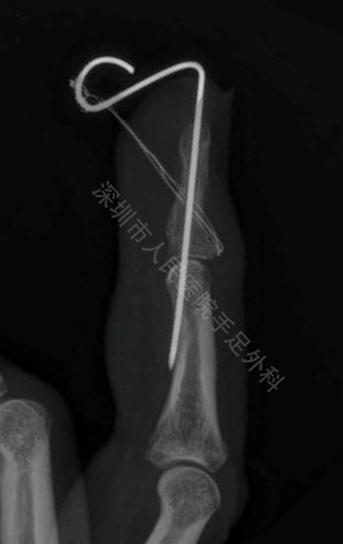

克氏针悬吊法

采用克氏针悬吊法,术后7周骨折愈合好。